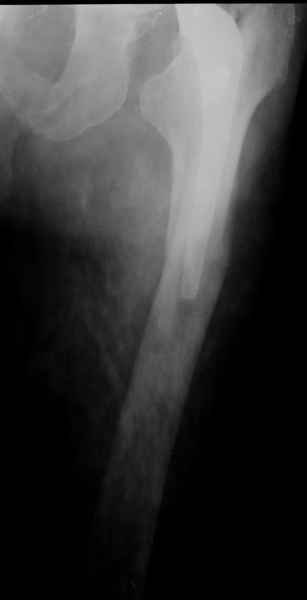

Закрытый остеосинтез-удлинение ножки (подход далеко не общепринятый, и пока даже не общеизвестный)- наименее инвазивный вариант, который обеспечивает немедленное восстановление опороспособности. Конечно, хотелось бы, чтобы эта операция решила проблему окончательно, т.е. в

ближайшие годы других больших операций не потребовалось бы.

ножка просела немного (вопрос, много - это сколько?)перечисленные проблемы - не самое важное сейчас, на них можно закрыть глаза. Ножка явно нестабильна, проксимальный отломок с б/вертелом к гвоздю не прицепить, срастется ли он с ножкой

1.Остеосинтез на ножке. Мне кажется, что применительно к этому случаю малоперспективный вариант. Синтез хорош, когда можно его выполнить в малоинвазивном исполнении и достигнуть стабильности. Действительно, если ножка б/цементной фиксации после этого не будет иметь фиксации, то ревизия не будет иметь проблем. В представленном случае стабильность синтеза сомнительная, а проведение доп.иммобилизации приведет к контрактуре суставов.